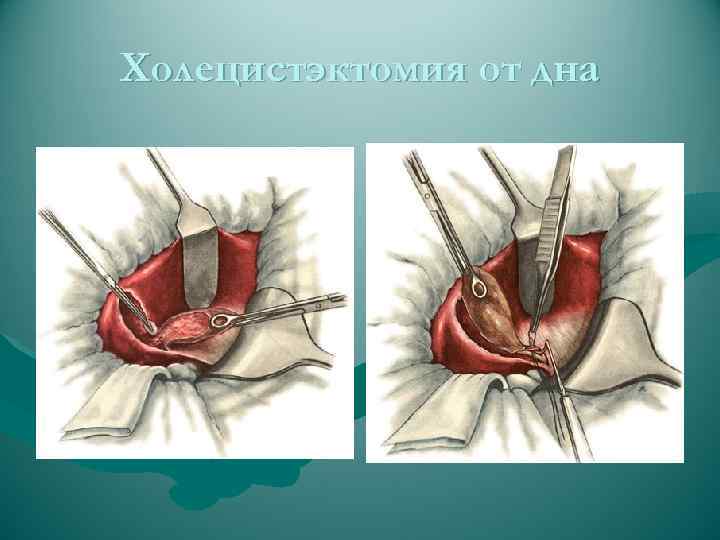

Холецистэктомия от дна

Холецистэктомия от дна

Холецистэктомия от дна

Холецистэктомия от дна